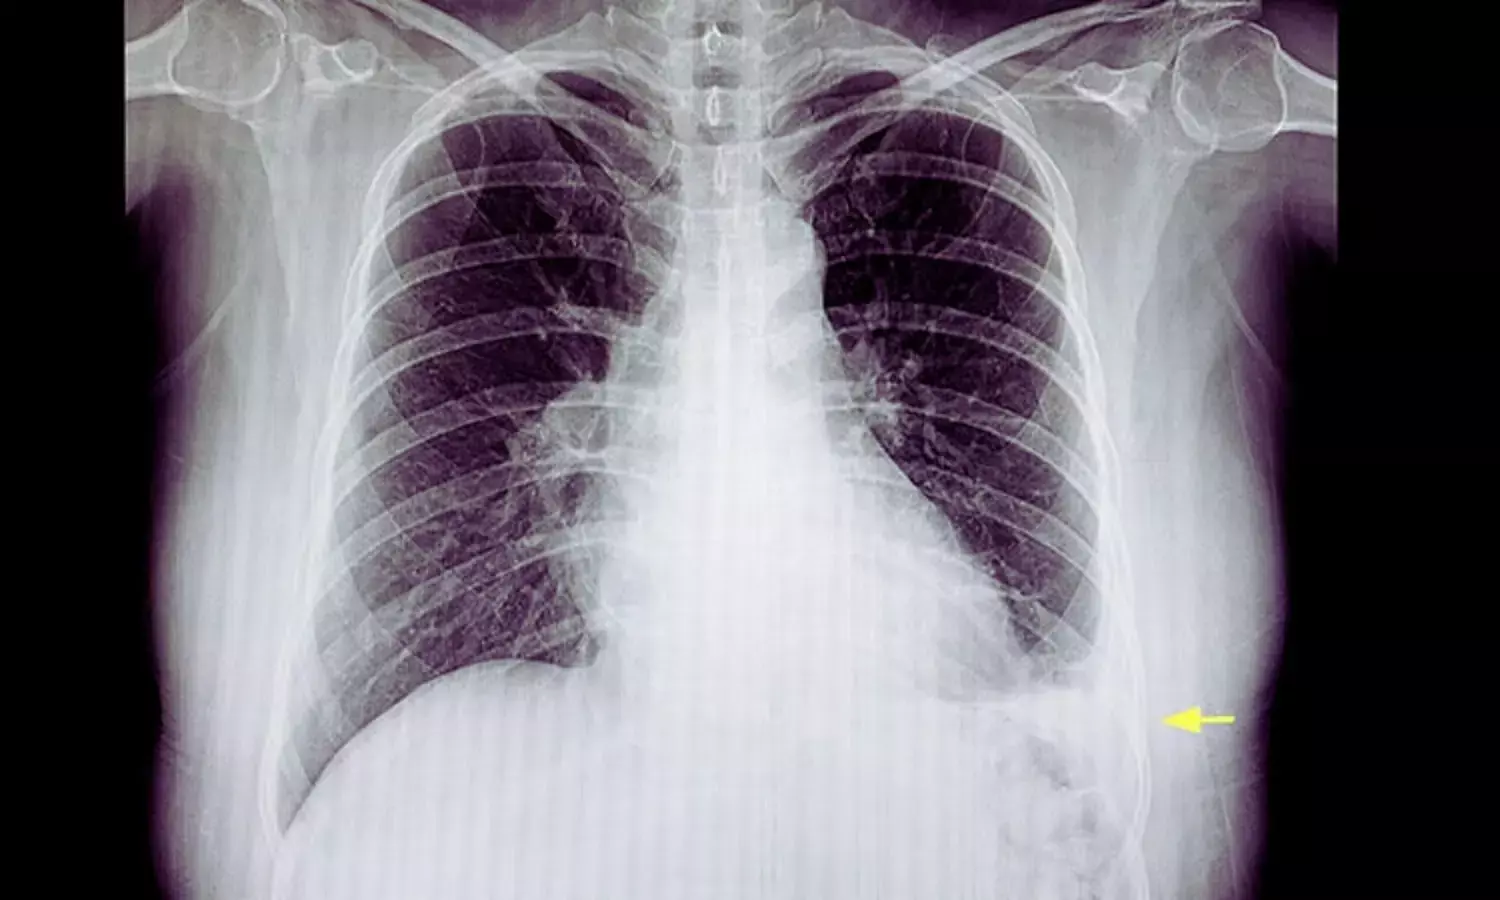

Pleural infection, including complicated parapneumonic effusion and Empyema, often requires chest tube drainage along with antibiotic therapy. Intrapleural enzyme therapy—commonly involving fibrinolytics and DNase—is frequently used to enhance fluid drainage by breaking down fibrinous septations and reducing fluid viscosity. However, the clinical value of saline lavage, either as a standalone treatment or combined with enzyme therapy, has remained unclear.

The primary outcome was the duration of pleural drainage, measured from randomization until chest tube removal. Secondary outcomes included radiographic reduction of pleural effusion on days two and five, length of hospital stay, and mortality or adverse events within 90 days.